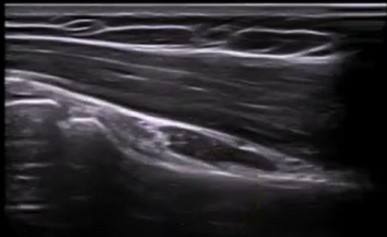

Lo haremos de forma longitudinal, siguiendo todo el vientre muscular hasta llegar a la zona tendinosa. De forma que obtendremos la siguiente imagen:

Una de las claves para explorar correctamente este tendón, será girar nuestra sonda 90º una vez hemos localizado en el corte anterior al tendón.

De esta forma obtendremos la siguiente imagen ecográfica: